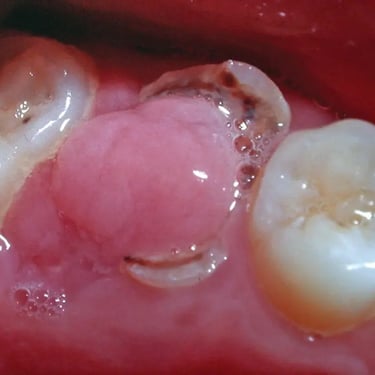

Pulpitis Crónica Hiperplásica

La pulpitis crónica hiperplásica es una inflamación de la pulpa con crecimiento excesivo de tejido pulpar a través de una caries abierta.

Los pacientes notan un tejido rojo que sobresale de la cavidad dental.

El tratamiento incluye la eliminación del tejido afectado y un tratamiento de conducto. Es crucial tratar la caries para evitar infecciones adicionales.